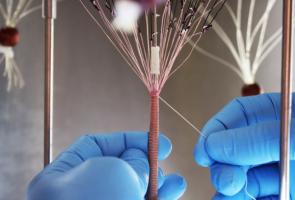

Actualité publiée le 17/02/2020MÉDECINE RÉGÉNÉRATIVE : Du fil humain pour raccommoder les vaisseaux